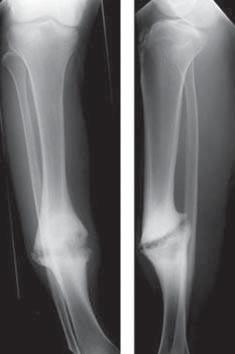

Пріоновий білок (позначається PrP) у людини кодується геном PRNP, локус якого розташований у короткому плечі хромосоми 20, та в результаті дозрівання містить 208 амінокислотних залишків. У нормальній формі, яка називається клітинною (PrPС), цей білок є компонентом клітинних мембран. Остаточно його роль не з’ясована, але важливо, що найвищу концентрацію він має в нервових клітинах. Патологічна форма пріонового білка (PrPSC) утворюється внаслідок посттрансляційних перетворень і, як правило, характеризується переходом α-спіралей білка в β-складчатість (рис. 29). Уражена патологічною формою цього білка ділянка мозку має характерну губчасту структуру внаслідок руйнування (рис. 30).

Рис. 30. Гістологічний

тури,

ваної тварини або людини.